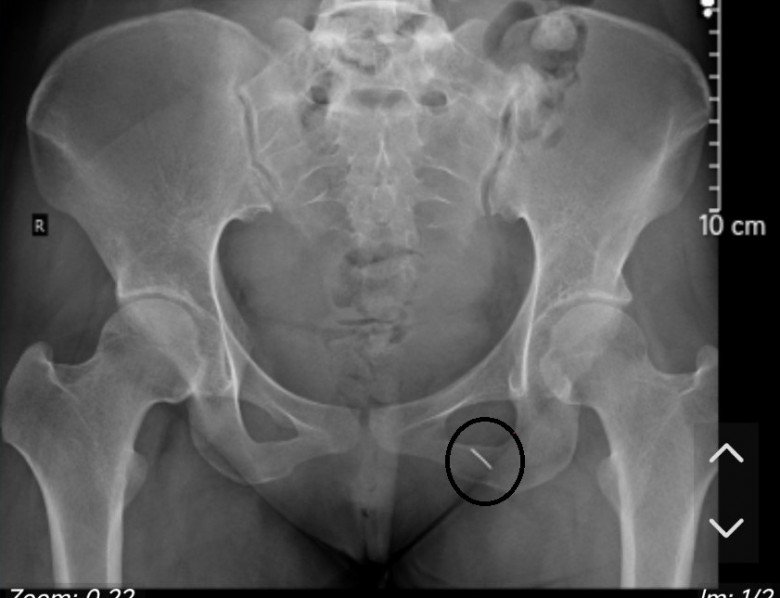

Hình ảnh chiếc kim khâu qua phim chụp và cô dâu sau khi được các bác sĩ xử lý.

Khai thác tiền sử bệnh án, người bệnh có nghi ngờ ngồi vào chiếc kim khâu may vá dài 5cm. Tuy nhiên, do người bệnh đang mang thai nên không thể tiếp xúc với tia X nên các bác sĩ cân nhắc việc chỉ định chụp X-quang định vị dị vật. Sau khi tham vấn các bác sĩ khoa Chẩn đoán hình ảnh, người bệnh được mặc áo chì, chụp đúng phần mông trái để xác định chính xác có bị dị vật đâm vào người hay không.

Kết quả phát hiện chiếc kim nằm sâu trong mông trái bệnh nhân. Chỉ sau 5 phút gây tê, các bác sĩ đã lấy ra một chiếc kim khâu dài 5cm, chưa hoen rỉ nằm sâu trong cơ mông của người bệnh.